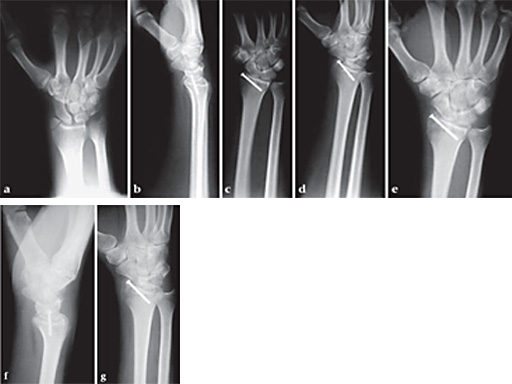

34-year-old patient, radial styloid fracture, good bone quality, 1.2 mm screw used.

a Preoperative x-ray.

b Follow-up after 1 week, AP view.

c Follow-up after 1 week, lateral view.

d Follow-up after 1 week, oblique view.

e Follow-up after 4 weeks, AP view.

f Follow-up after 4 weeks, lateral view.

g Follow-up after 4 weeks, oblique view.